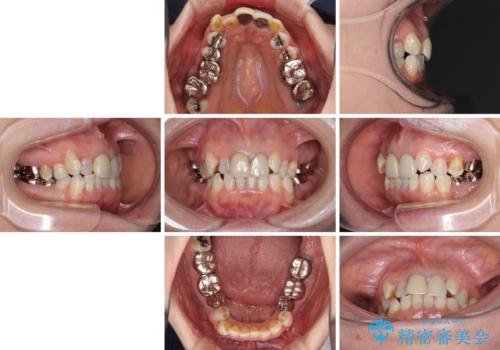

- 全顎的な歯列不正と、銀歯だらけの奥歯を気にして来院された患者様です。

奥歯の銀歯は、セラミッククラウンを装着するには歯の高さが不十分であり、そのままでは矯正治療を行うことが困難であるため、歯冠長延長術を行うこととしました。

また、根管治療の必要な歯がいくつかあるため、歯周外科治療の治癒期間を利用して根管治療を行い、その後インビザラインにて矯正治療を行うこととしました。

矯正治療後にはオールセラミッククラウンにて補綴治療を行うこととしました。

歯冠長延長術を行ったことで、自然な形態かつ清掃性の高いセラミッククラウンを装着することができました。

全顎的に治療を行ったため、治療期間も費用も負担は大きくなりましたが、統一感のある仕上がりとなりました。